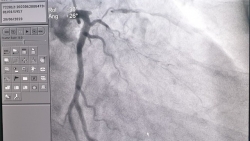

Người đàn ông hút thuốc lá lâu năm, tình cờ phát hiện bị hẹp động mạch vành

Sau một lần đi khám sức khỏe định kỳ tại Bệnh viện 108, người đàn ông hút thuốc lá lâu năm phát hiện bản thân bị hẹp khít mạn tính động mạch vành.